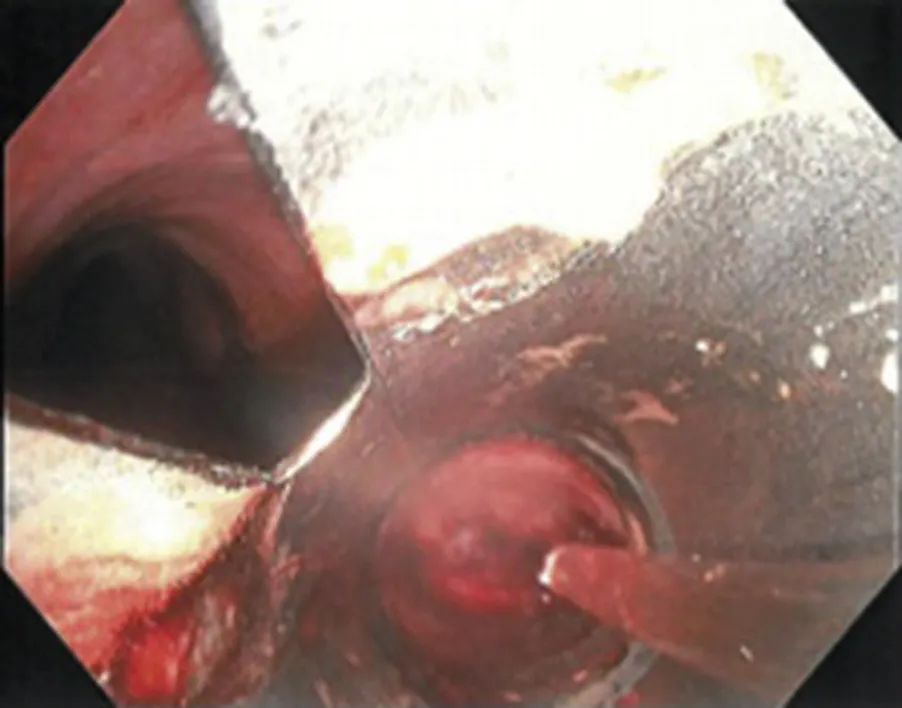

建立人工气道。由于大部分大咯血来源于气道损伤,因此通过胸部影像学检查或支气管镜检查(通常使用硬质支气管镜)明确出血部位将为后续的治疗提供便利。

稀释液都被认为会引起局部血管收缩,在无严格证据的情况下被广泛使用。使用冰生理盐水已是较为普遍的做法,但是滴注的冰生理盐水量通常较小。与冰生理盐水相比,支气管内使用肾上腺素的疗法受到质疑,尤其是对冠状动脉痉挛和心律失常

的患者。